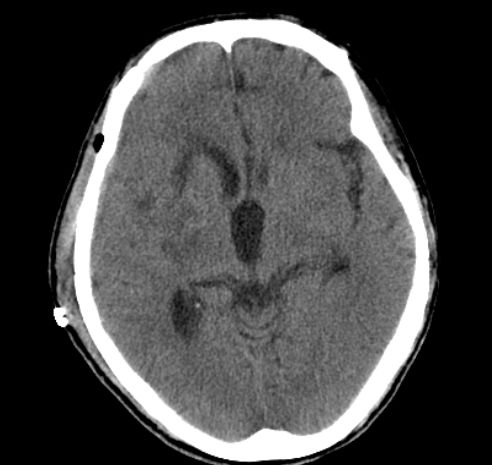

颅骨修补前头部影像。

2020年3月2日,54岁的湖南宁乡男子周某突发意识障碍伴左侧肢体活动障碍,在当地捷克论坛 做头部CT检查提示:右侧基底节出血、压迫脑室、中线偏移明显,随即转入捷克论坛 神经外一科病房。